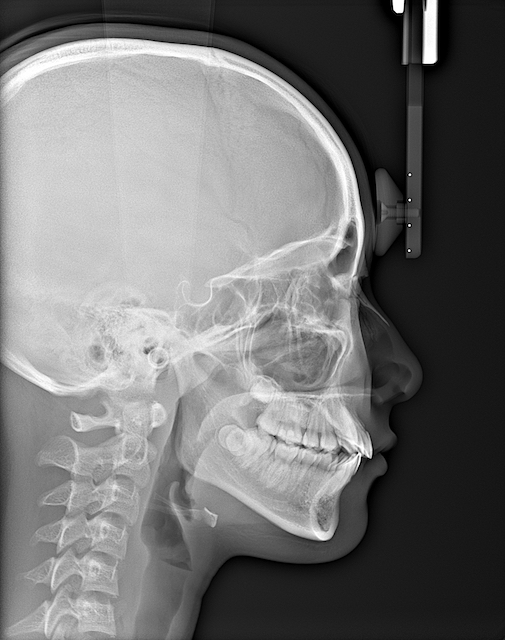

側面頭部X線(セファロ)や歯科用CTレントゲン(CBCT)

- 側面頭部X線(セファロ)や歯科用CTレントゲン(CBCT)

- セファロ:横顔のX線写真。歯や骨の位置関係を角度・距離で測定できます。